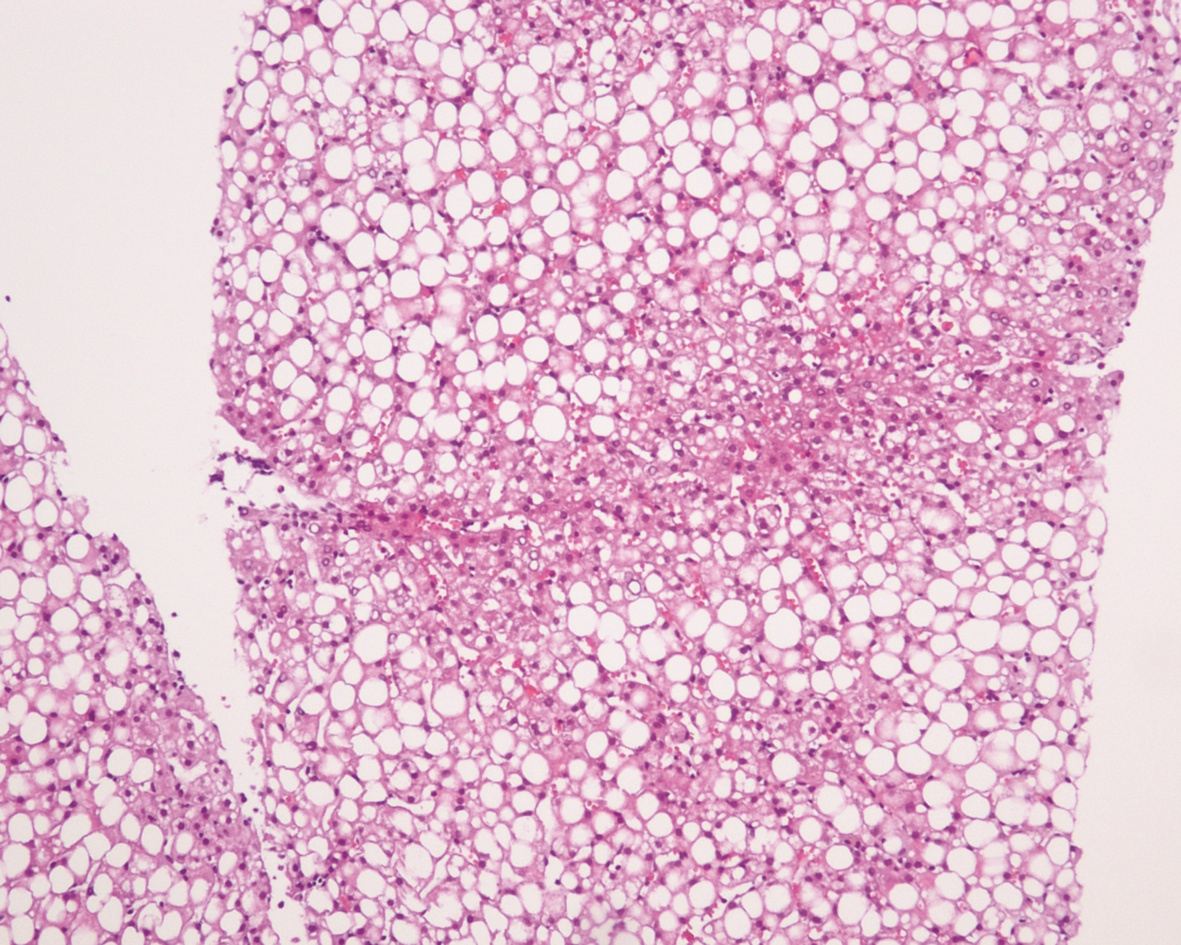

Hepatocellular carcinoma with bile duct tumor thrombus: A case report

Renjie LU, Fangfang SUN, Jie DU, Lirong ZHAO

2022, 38(8): 1872-1874. DOI: 10.3969/j.issn.1001-5256.2022.08.028

Abstract(831) HTML (461) PDF (3665KB)(88)

Abstract: